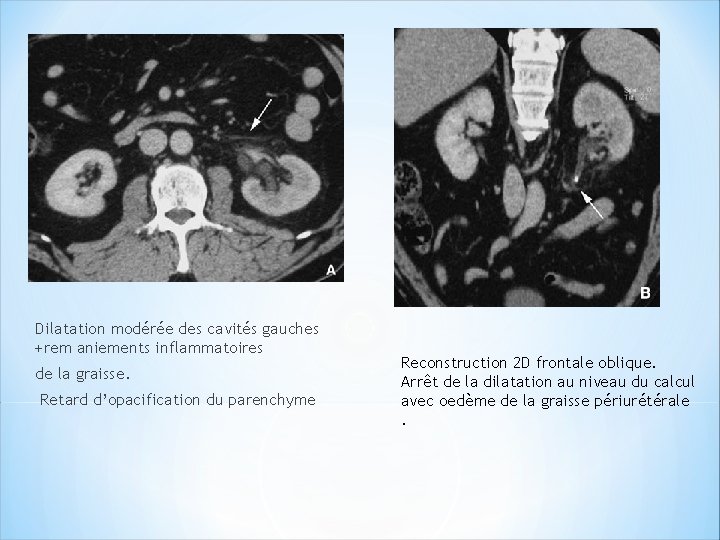

Dilatation modérée des cavités gauches +rem aniements inflammatoires de la graisse. Retard d’opacification du parenchyme Reconstruction 2 D frontale oblique. Arrêt de la dilatation au niveau du calcul avec oedème de la graisse périurétérale.

Colique néphrétique gauche. Obstruction urinaire modérée. Reconstruction frontale oblique dans l’axe de l’uretère. montre la dilatation urétérale qui s’arrête sur le calcul